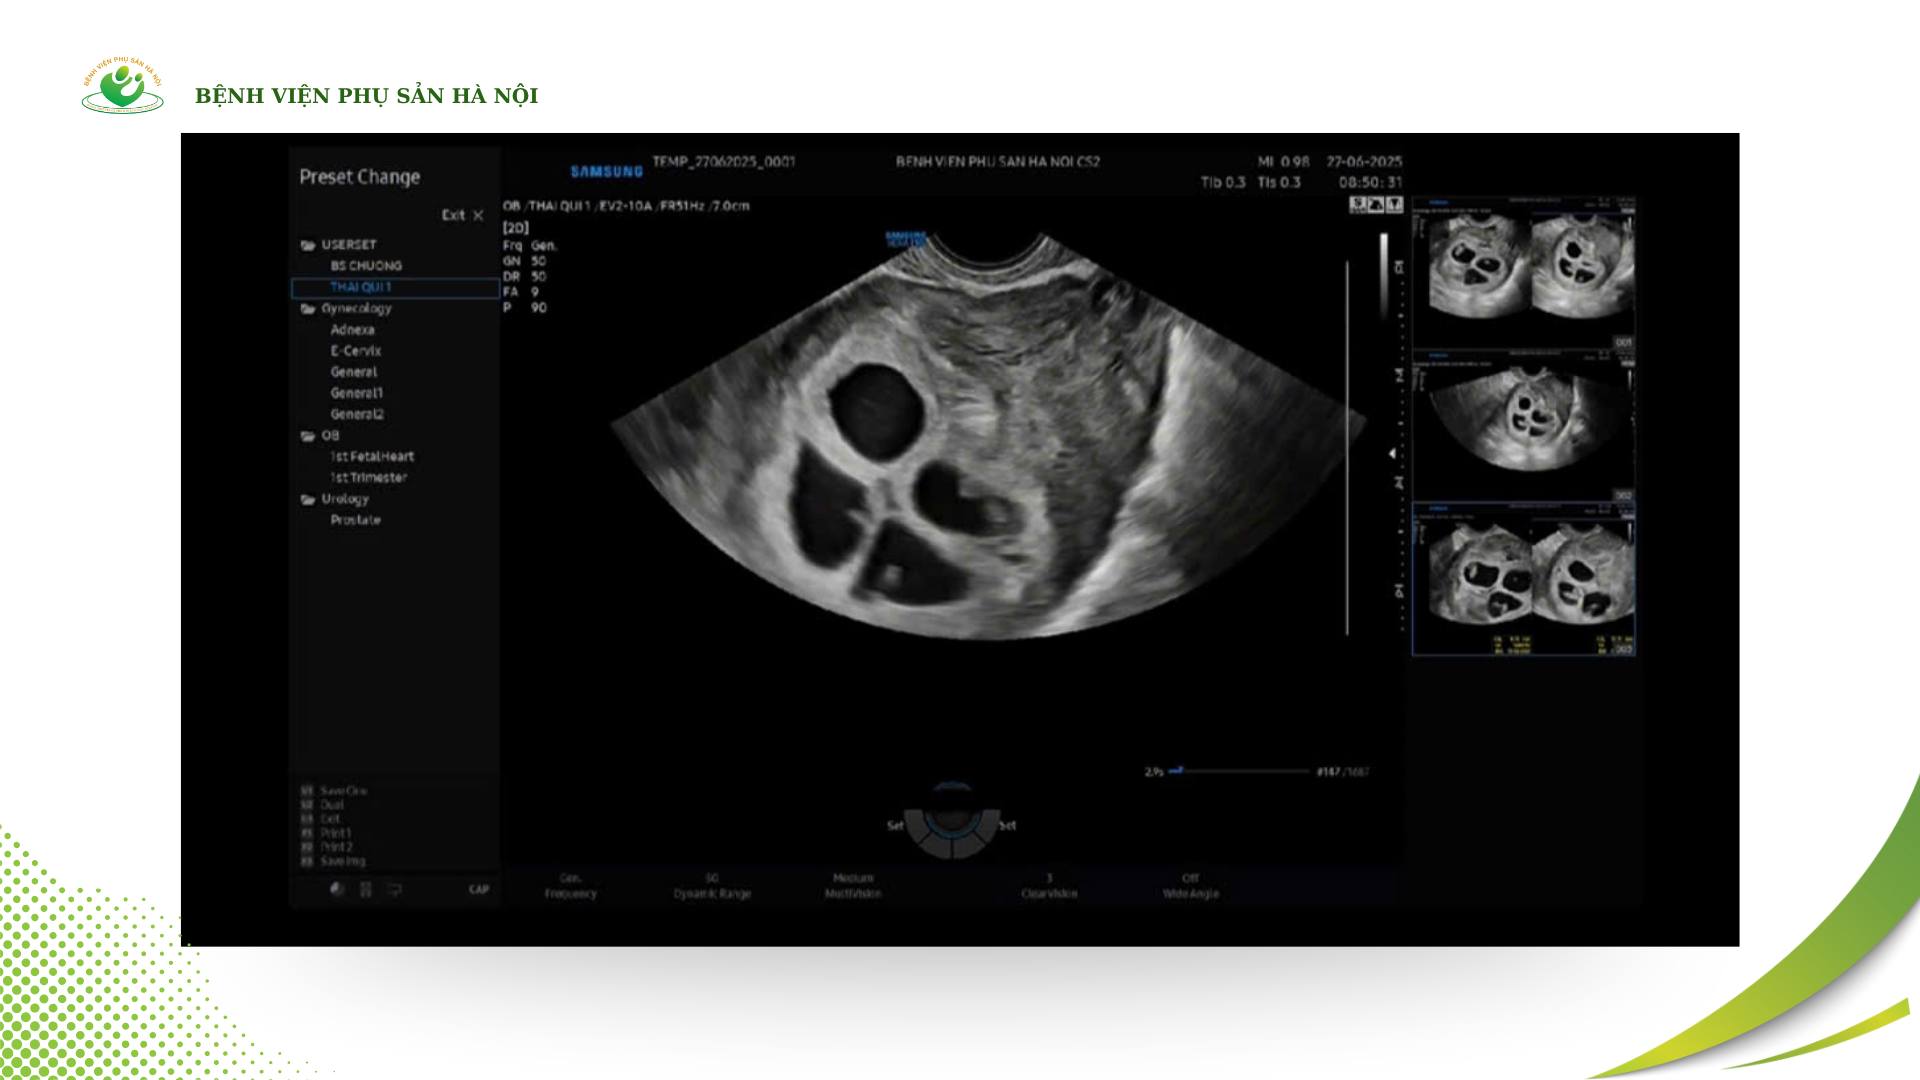

Mới đây, các bác sĩ tại Cơ sở 2 – Bệnh viện Phụ Sản Hà Nội đã ghi nhận một trường hợp mang thai tự nhiên hiếm gặp: sản phụ mang 4 thai tự nhiên cùng lúc mà không có can thiệp hỗ trợ sinh sản. Đây được xem là một tình huống đặc biệt trong y văn sản khoa, khi tỷ lệ xảy ra chỉ khoảng 1 trên 700.000 đến 800.000 ca mang thai tự nhiên.

Ngay sau khi tiếp nhận, đội ngũ bác sĩ của bệnh viện đã tiến hành siêu âm và theo dõi sát sao tình trạng thai kỳ. Kết quả thăm khám ban đầu cho thấy cả bốn thai đều có tim thai rõ ràng, phát triển phù hợp với tuổi thai và chưa ghi nhận dấu hiệu bất thường.

Cực hiếm gặp: Bệnh viện Phụ Sản Hà Nội ghi nhận 1 sản phụ mang thai 4 tự nhiên, tỷ lệ chỉ khoảng 1/700.000 - 800.000 ca- Ảnh 1.